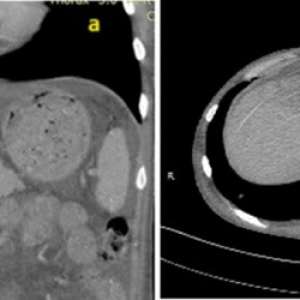

Симптомная доброкачественная опухоль

Женщина, 59 лет

Обратилась с жалобами на боль в животе, потерю аппетита и рвоту без примеси желчи, которые беспокоят её в течение года. При осмотре живот был мягким и безболезненным, объемных образований при пальпации не определяется.

Выполнена ЭГДС, обнаружена язва размером 0,5 × 0,5 см в привратнике. Однако дальнейшее обследование было невозможно из-за деформации привратника. Взята биопсия изъязвленной слизистой. Заключение - хронический гастрит.

КТ (рис. 1): обнаружено чётко очерченное образование размером 2,5 × 3,0 см в головке поджелудочной железы, сдавливающее двенадцатиперстную кишку...